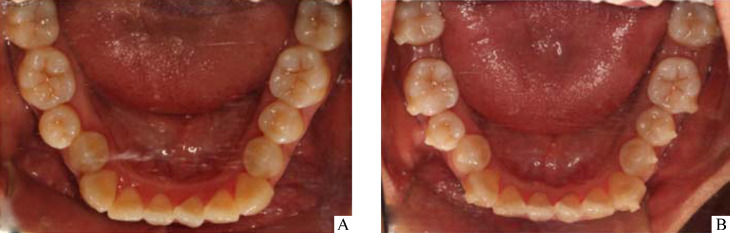

在Clincheck设计中所有磨牙的远中移动过程均采用“V”模式。每副矫治器佩戴时间为10 d,每日佩戴时间不少于22 h。收集患者治疗前(T0)和下颌第1磨牙远移到位时(T1)CBCT影像资料及口内照片(图1)。

图1.

下颌牙列照

Figure 1 Photograph of mandibular dentition

A: Before therapy; B: Mandibular molar distalization